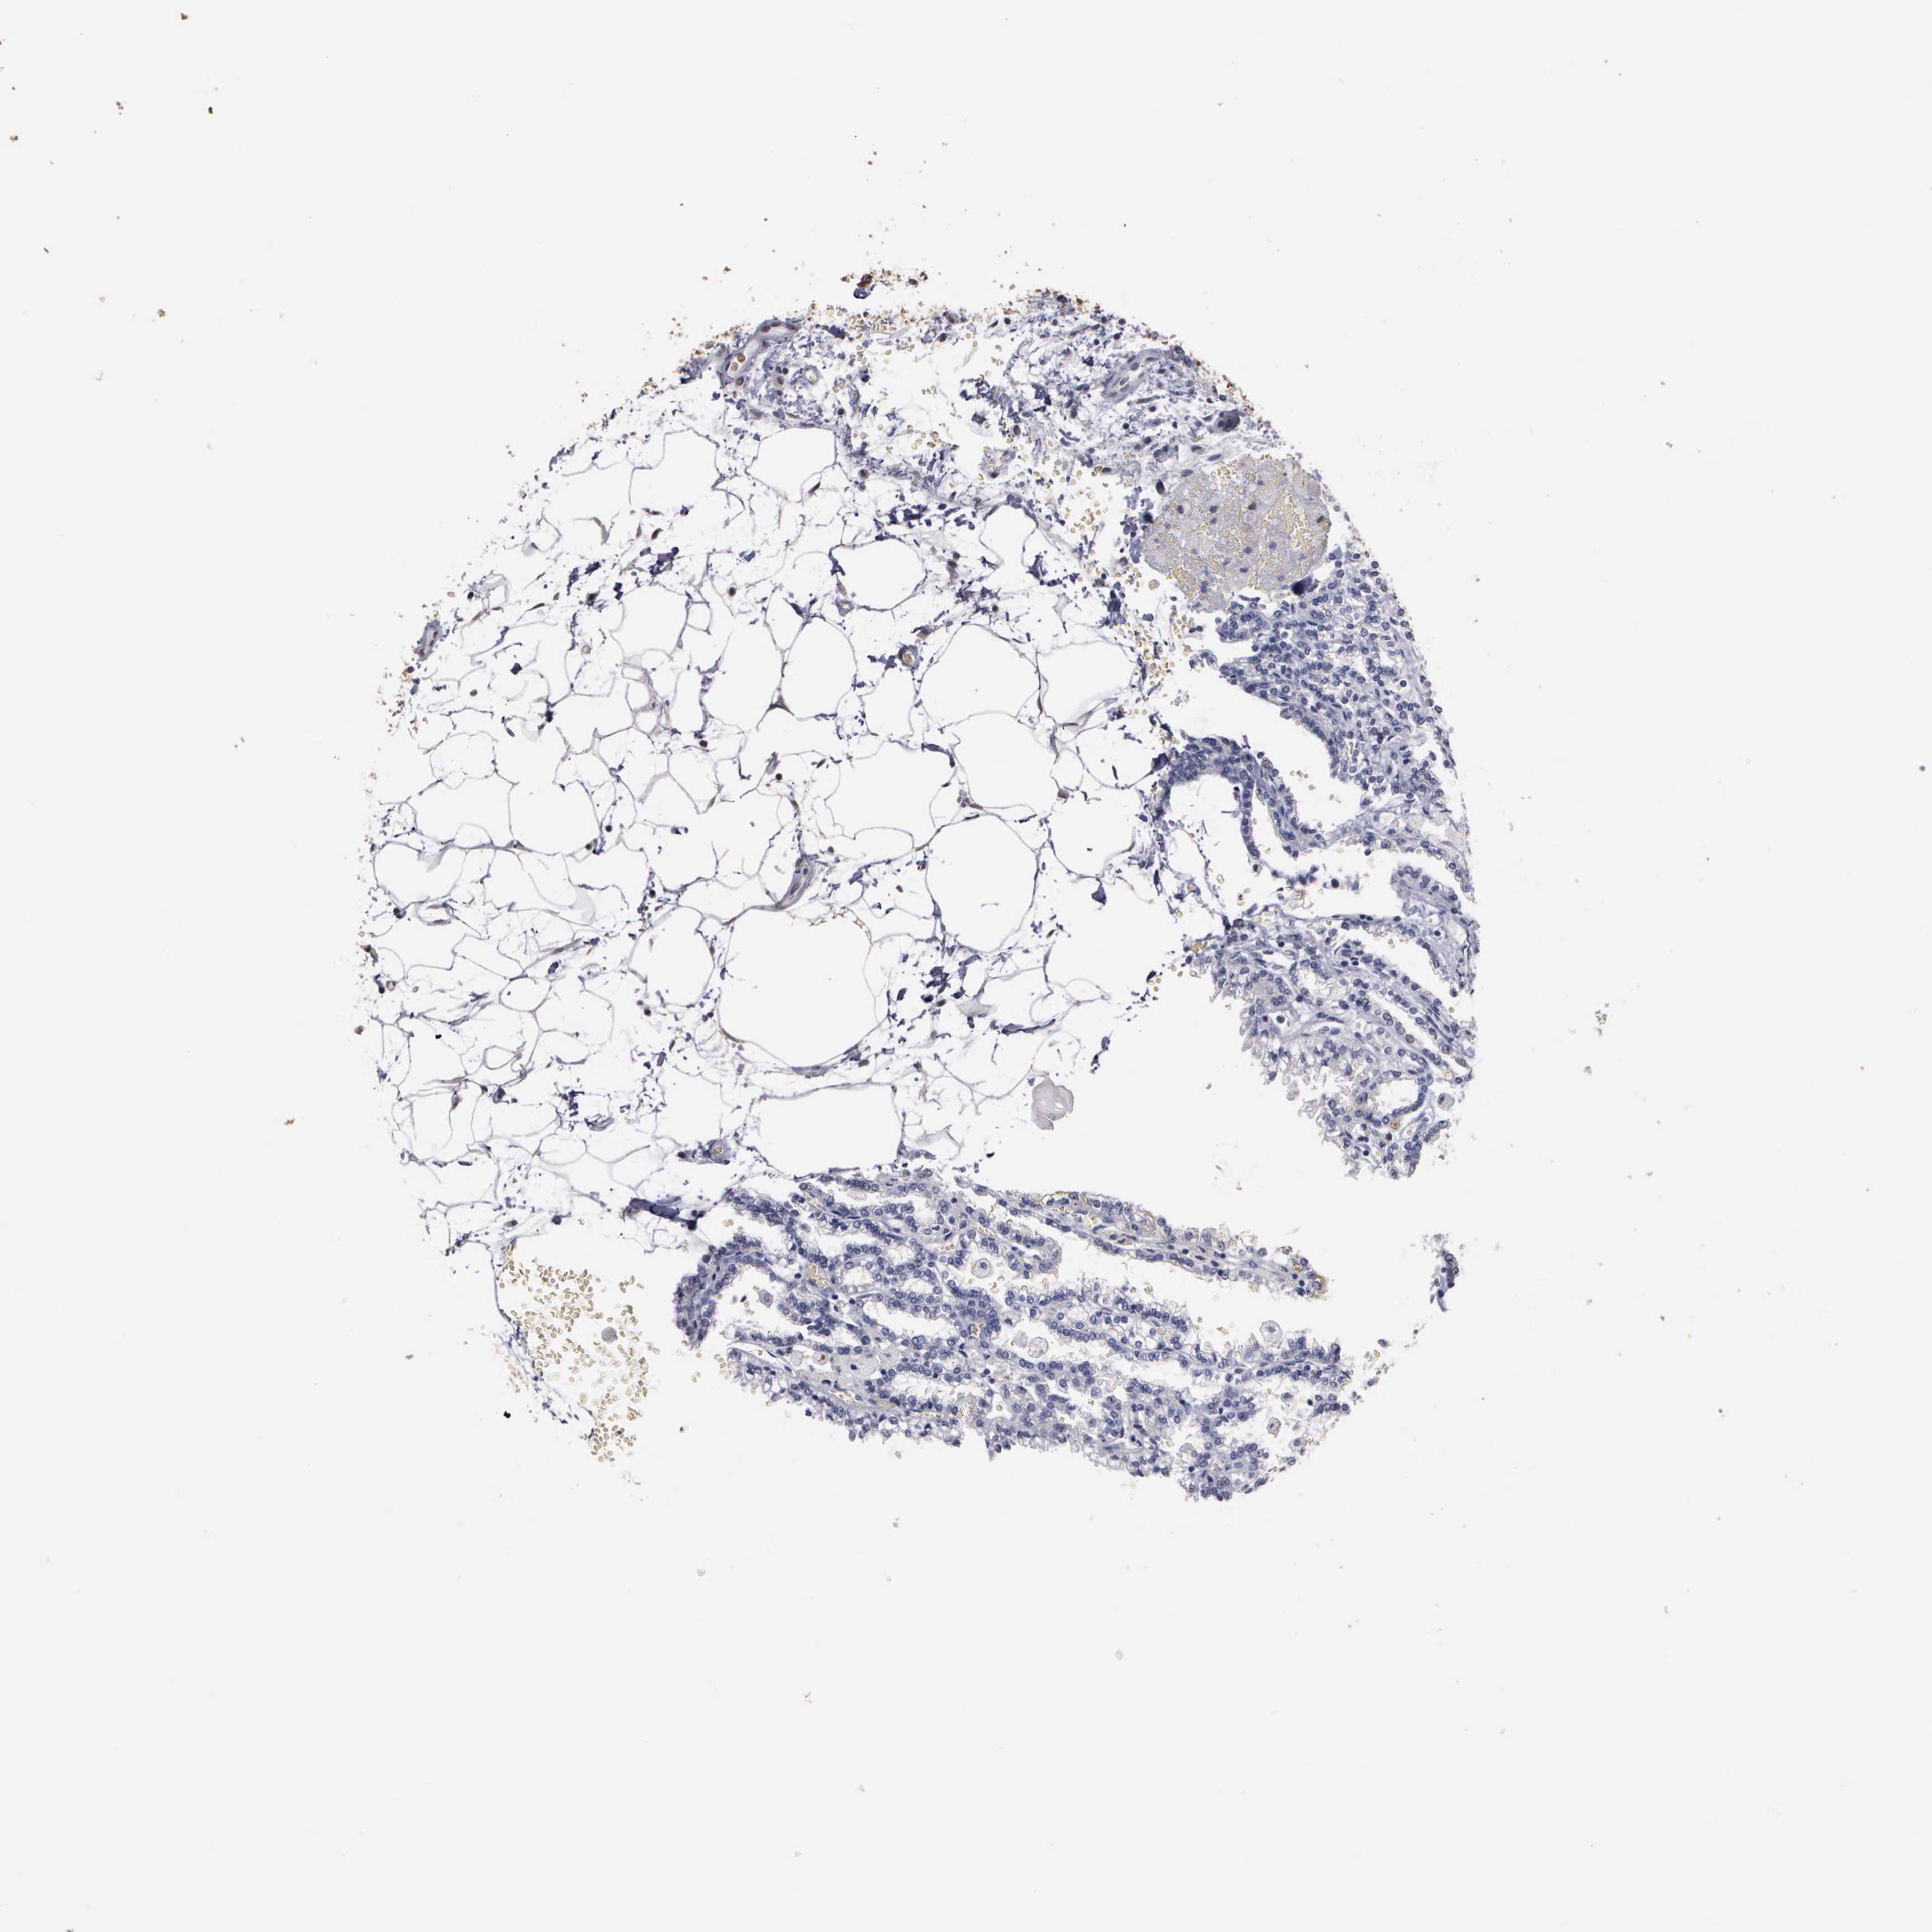

CANCER RENAL CANCER Show tissue menu

KICH TCGA KIRC TCGA KIRC VALIDATION KIRP TCGA PROTEIN RCC CPTAC PROTEIN EXPRESSION